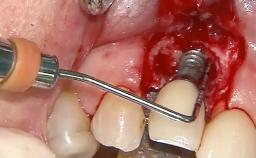

A 30-year-old patient presented at our clinic with a chief complaint of pain in her endodontically treated right maxillary central incisor (tooth 11) with a post-and-core and a fixed single crown. She had a very high lip line, a medium to thin soft-tissue phenotype, and a medium scalloped gingival contour. She also had high esthetic expectations because of her young age and beautiful smile. However, her expectations were realistic and she understood the risks of the treatment. At the initial clinical examination there was a slight mobility of tooth 11; no fistula was observed. The patient also had a single crown on the adjacent tooth 21. Both restorations were old and esthetically deficient. A digital periapical radiograph showed a very small periapical radiolucency, a thick intraradicular post, and no separation between root fragments.